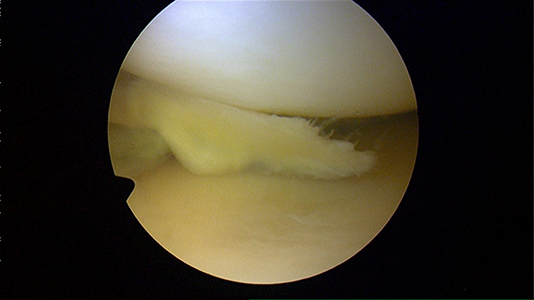

C. Les microfractures pour réparer le cartilage

Définition: réparation d’une lésion cartilagineuse par la réalisation d’orifices favorisant la formation d’un tissu fibrocartilagineux, une sorte de patch.

Suites opératoires : la revalidation nécessite une absence d’appui pendant 6 semaines puis le port d’une attelle de décharge pendant 6 semaines